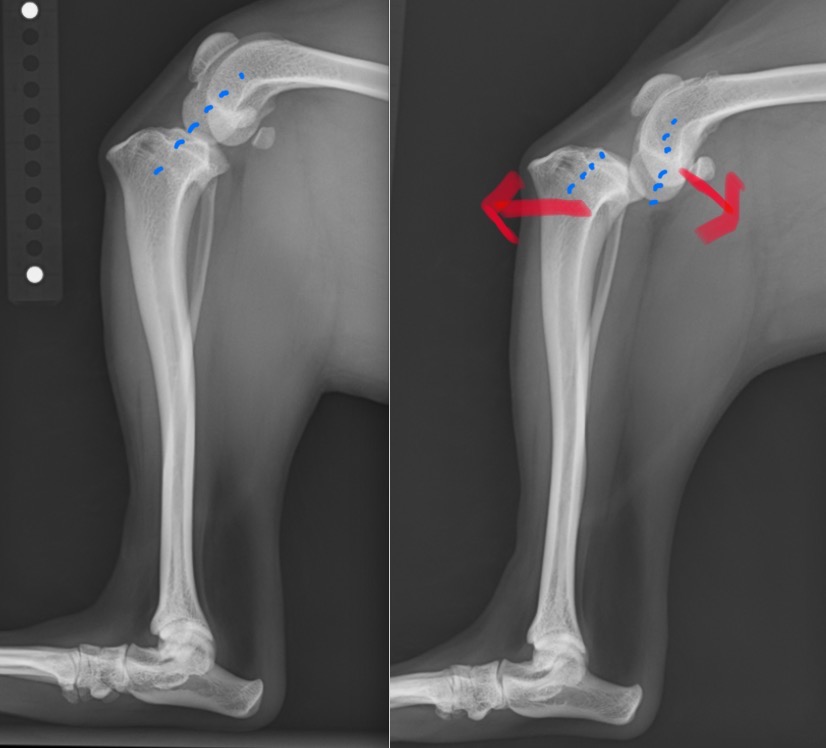

日常的に膝蓋骨が脱臼する子は常に膝が内側に引っ張られるような力がかかっており、膝の中にある前十字靭帯に過剰な負荷がかかっていることが多くあります。(赤矢印)

前十字靭帯が損傷すると膝関節が不安定になり、ももの骨とすねの骨が前後にずれるような状態になります。

左:正常膝関節 / 右:前十字靭帯を損傷し不安定性が見られる膝関節